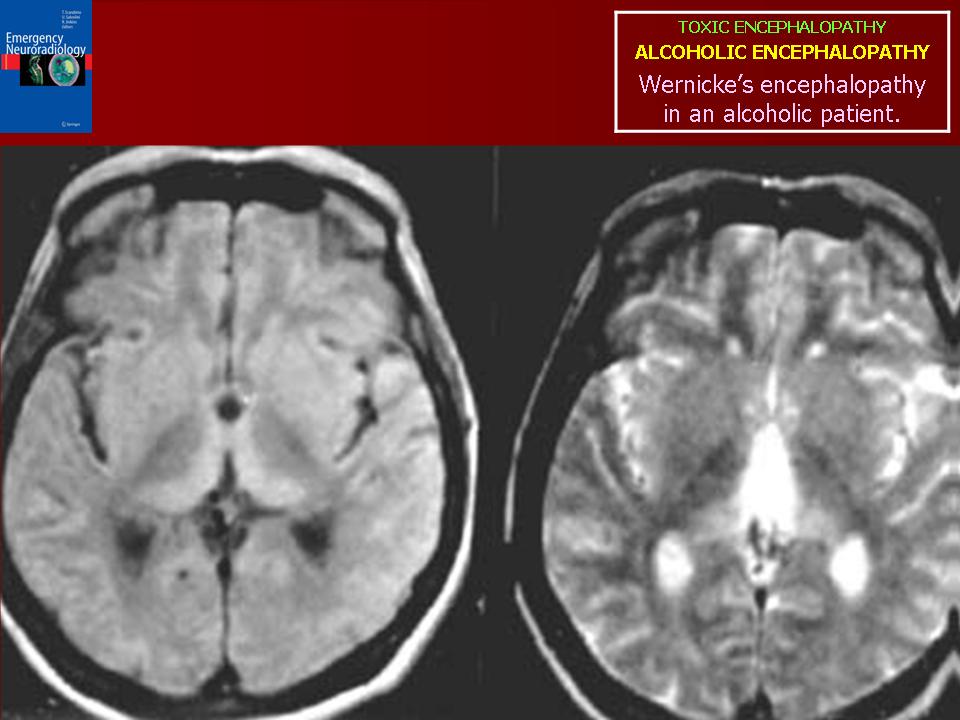

Энцефалопатии токсикогенные

Спасибо, Валентин Львович! Алькогольную встречал несколько раз, у относительно молодых пациентов. Без анамнеза и клинической картины, энцефалопатии очень сложно дифференцировать, если не попадется патогманичного признака.